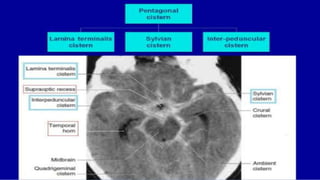

Cisterns of brain

The subarachnoid cisterns, or basal cisterns, are compartments

within the subarachnoid space where the pia mater and

arachnoid membrane are not in close approximation and

cerebrospinal fluid (CSF) forms pools or cisterns (Latin: "box").

Pre pontine cisterns

Suprasellar cistern